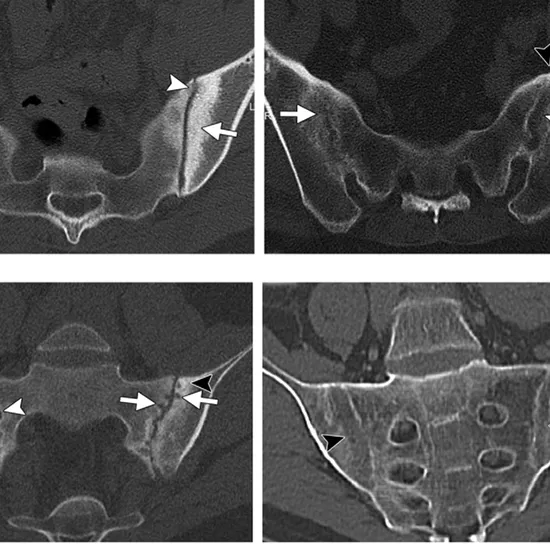

The SI Joint is a triangular bone at the base of the spine that connects to the left and right iliac bones of the pelvis. A CECT SI Joint (Contrast Enhanced Computerized Tomography sacroiliac joints) is an imaging method used to evaluate sacroiliac joint problems and injuries (SI Joints). To obtain cross-section images of the SI joints, this scanning procedure employs rotating x-ray beams and injects contrast material into the patient. The images assist the doctor in determining the proper functioning of the SI joints.

• To detect sacrum and iliac bone fractures

• To determine the source of persistent lower back pain

• To detect bone and joint inflammation

• To identify a joint and bone infection

• Detection of masses in the sacroiliac